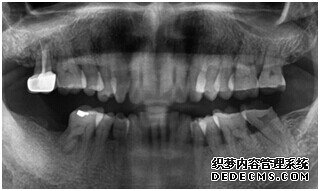

种植体成功植入后的CT效果图

整个种植牙完成后的效果图

种植牙整个过程完成后,刘女士非常满意自己的牙齿,并且表示以后一定会遵照医生的嘱咐好好注意自己的口腔健康,每晚一定会好好刷牙,饭后漱口,当然也会注意保护这颗种植牙!